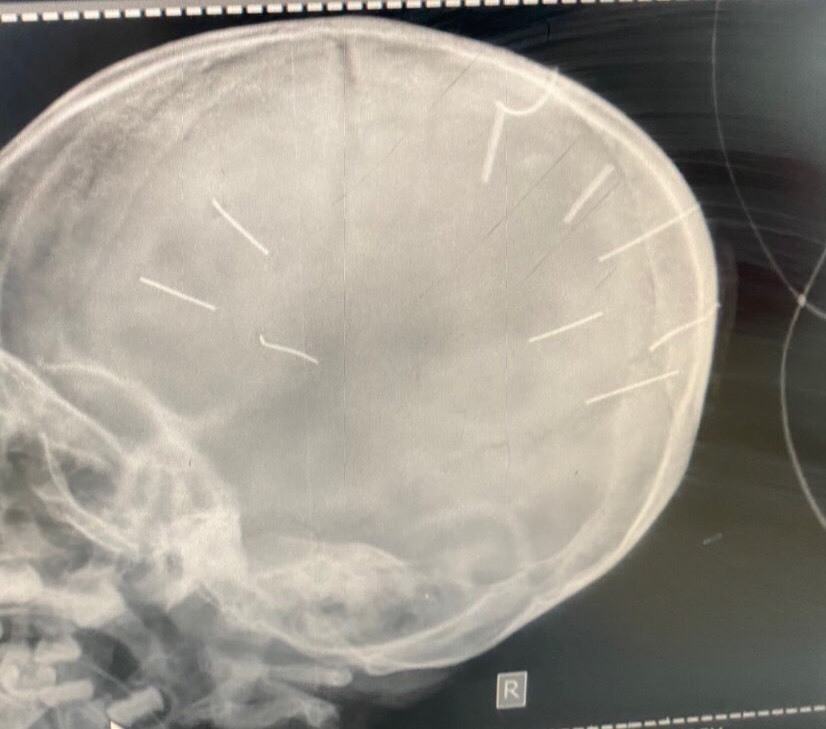

| Hình ảnh chụp cắt lớp nhận thấy sọ của cháu A. như bị đóng đinh vào đầu. |

Các bác sĩ khoa Cấp cứu, Bệnh viện Đa khoa huyện Thạch Thất đã đặt ống, chụp phim làm chẩn đoán, thấy trên phim có hình ảnh cản quang trên hộp sọ bệnh nhi.

Hình ảnh chụp cắt lớp nhận thấy, có những hình ảnh như đinh bắn vào sọ của cháu A. Có khoảng 9 vật thể giống đinh cắm trong não bệnh nhân.